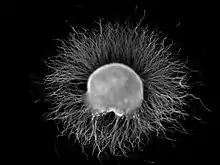

A ganglion (PL: ganglia) is a group of neuron cell bodies in the peripheral nervous system. In the somatic nervous system this includes dorsal root ganglia and trigeminal ganglia among a few others. In the autonomic nervous system there are both sympathetic and parasympathetic ganglia which contain the cell bodies of postganglionic sympathetic and parasympathetic neurons respectively.

Ganglia are primarily made up of somata and dendritic structures which are bundled or connected. Ganglia often interconnect with other ganglia to form a complex system of ganglia known as a plexus. Ganglia provide relay points and intermediary connections between different neurological structures in the body, such as the peripheral and central nervous systems.